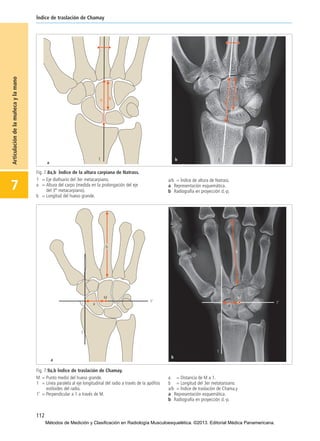

Fig. 7.8a,b Índice de la altura carpiana de Natrass.

1 = Eje diafisario del 3er metacarpiano.

a = Altura del carpo (medida en la prolongación del eje

del 3er

metacarpiano).

b = Longitud del hueso grande.

a/b = Índice de altura de Natrass.

a Representación esquemática.

b Radiografía en proyección d.-p.

Fig. 7.9a,b Índice de traslación de Chamay.

M = Punto medio del hueso grande.

1 = Línea paralela al eje longitudinal del radio a través de la apófisis

estiloides del radio.

1’ = Perpendicular a 1 a través de M.

a = Distancia de M a 1.

b = Longitud del 3er metatarsiano.

a/b = Índice de traslación de Chama.y

Índice de altura de Natrass

El índice de Natrass representa el cociente entre la altura del

carpo (a) y la longitud del hueso grande o capital (b) (Fig. 7.8).

Primero se establece el eje longitudinal del 3er metacarpiano,

a partir del cual se mide la altura del carpo como distancia entre

la base del 3er metacarpiano y la superficie de la articulación

distal del radio. La longitud del hueso grande se determina

como una mayor distancia entre la superficie articular proximal

Índice de traslación de Chamay

Un aumento de la desviación del carpo se puede ocasionar en

el marco de enfermedades degenerativas, destructivas inflama-

torias y postraumáticas. Estas anomalías posicionales se

pueden cuantificar mediante el índice de traslación de Chamay

(Fig. 7.9). Para ello se establece primero el centro de la cabeza

del hueso grande.A partir de ahí se mide la distancia hasta una

perpendicular que transcurre a través de la apófisis estiloides

del radio. Entonces se calcula el cociente entre este trayecto y

la longitud del 3er metacarpiano (b).

Valor normal: a/b = 1,57 ± 0,03 Índice de traslación de Chamay

Valor normal: a/b = 0,28 ± 0,03

Valores patológicos: a/b > 0,31